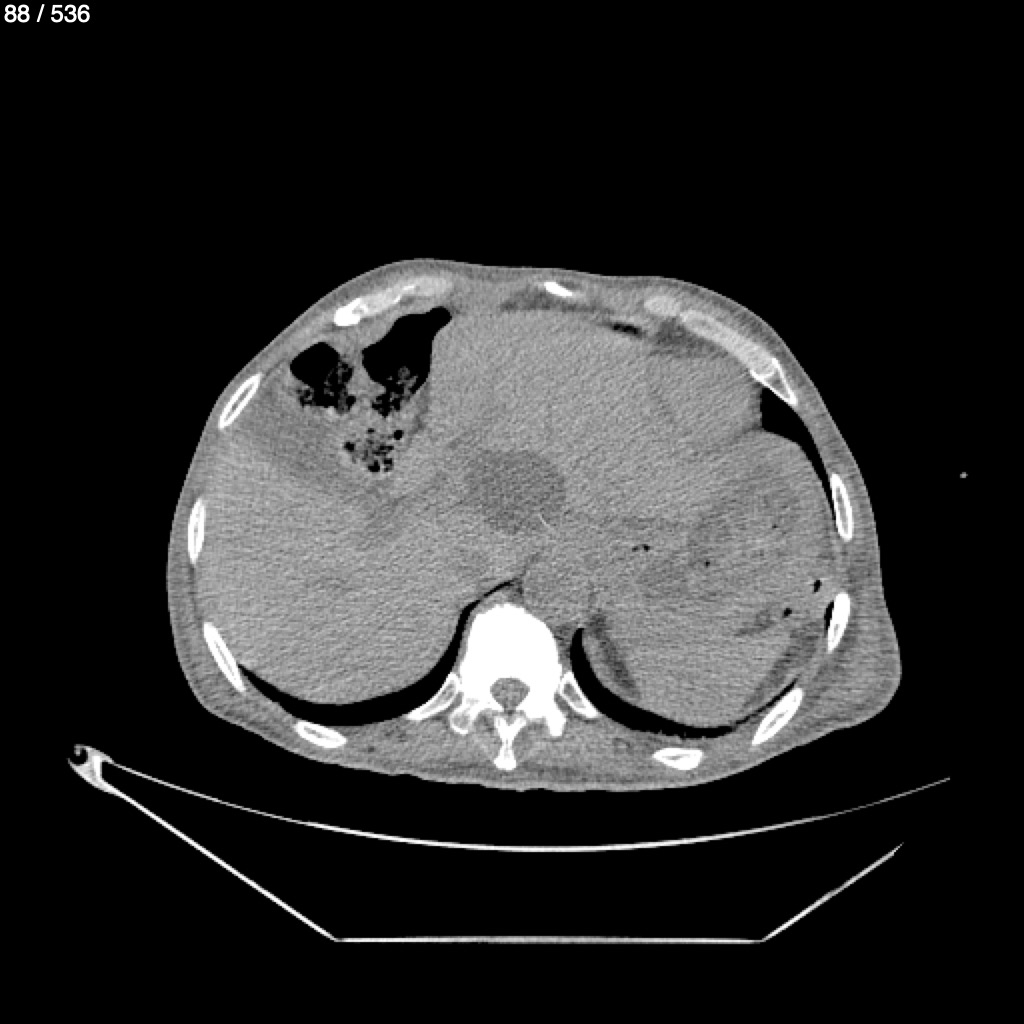

Angel Villalobos Palomeque 73 A - T.C Abdomen Simple